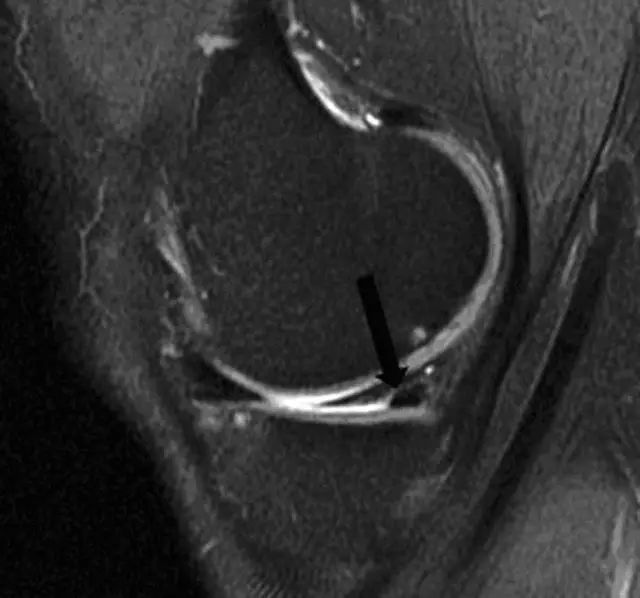

图 11 内侧半月板桶柄状撕裂——双后交叉韧带征

左图:经髁间切迹的矢状面,可见剥离开的低信号半月板块(白色箭头)平行于正常的后交叉韧带(黑色箭头)。右图:冠状面可见剥离的半月板块(白色直箭头),在正常的后交叉韧带(黑色箭头)下方。残留的半月板外缘(白色圆箭头)形态异常且比正常(对侧)的小。